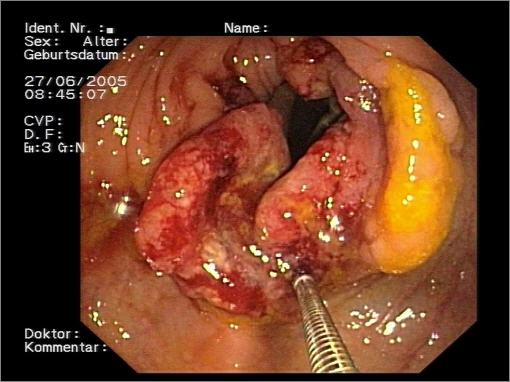

Darmkrebsgefahr durch schlechte Lebensmittel

Allgemein ist die Meinung vorherrschend, dass der Genuss von Tabak an erster Stelle der krebsauslösenden Ursachen steht. Mittlerweile ist dies nicht mehr der Fall. Auf dem ersten Rang steht der Genuss von Nahrung, der zum Ausbruch des Krebses führt. Beispielsweise sterben über 26.000 Menschen in Deutschland Jahr für Jahr an Darmkrebs, was ein deutlicher Hinweis darauf ist, dass die Lebensmittel in Deutschland massiv an Qualität verloren haben.